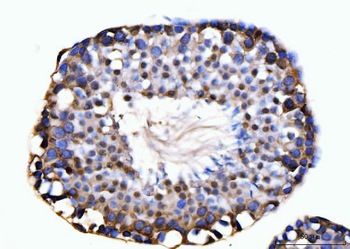

50 μl, 100 μl - MARK3 Recombinant Rabbit Monoclonal Antibody [orb704310]Featured

ICC, IF, IHC-Fr, IHC-P

Human, Mouse

Rat

Rabbit

Recombinant

Unconjugated

50 μl, 100 μl - Featured